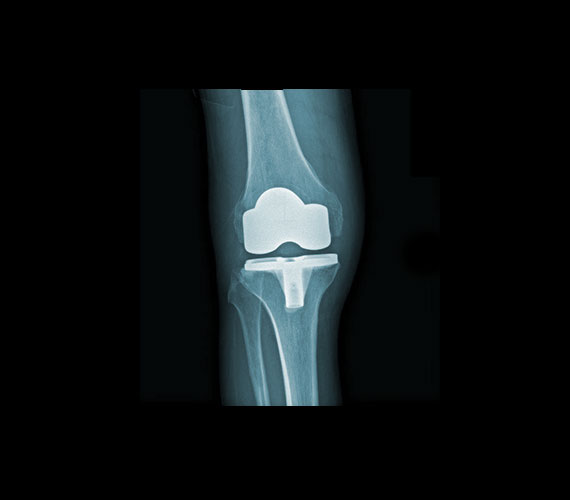

Protesi ginocchio post

PROTESI TOTALE

GINOCCHIO DESTRO